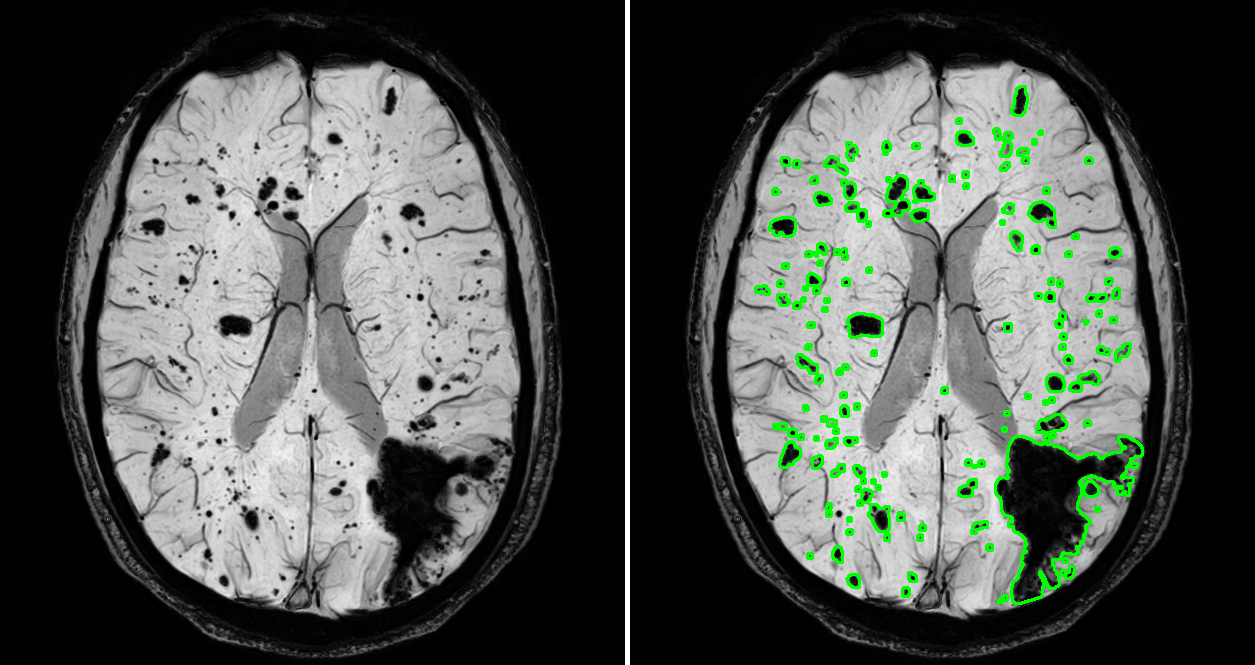

3.4.3 Quantitative analysis visualization

To facilitate lesion observation by clinicians, the contours of the lesions are delineated on the original FCCM images using the segmentation masks. Lesions are sequentially numbered, and visualization collages for the two examinations are generated. Additionally, we create a quantitative statistical table for lesion volumes, plot an overall disease assessment line chart based on the lesion volume information between different examinations, and calculate the proportion of lesion volume in different ranges. This ultimately forms a visualization framework to assist doctors in comprehensively analyzing disease progression. This framework enables physicians to quickly locate lesion areas and perform faster and more accurate quantitative assessments of lesion changes between different examinations, thus better understanding the progression of the patient’s condition. All the visualization results provided to physicians are presented in Table 1.

4.3 Quantitative statistics results

In the FCCM lesion quantitative statistics module, 2D segmentation results of lesions were first acquired, and then a 3D segmentation mask was synthesized for quantitative statistics. The statistical information included the number and volume of lesions, and a comparative statistics of lesions between two examinations of the same patient was conducted. The quantitative statistical results of a case were presented to demonstrate the effectiveness of the proposed lesion quantitative statistical module. Figure 7 showed the results of quantitative analysis visualization, where the numbering of each lesion and the contour of the lesion segmentation mask were plotted on the original FCCM image. The visualization collages of the entire volumes were shown in Figure 2 and Figure 3 in the Appendix A. The numberings and corresponding volume/volume pairs of lesions with a volume greater than 100 were presented in Table 3. The shaded areas depicted multiple lesions in the follow-up inspection that matched the same lesion in the previous inspection. This was mainly due to the irregular shape of the lesions, with discontinuities appearing in different planes. It manifested as a large lesion with several smaller lesions, resulting in a many-to-one situation. Figure 7 could help doctors more intuitively compare the lesion and its segmentation mask, assist in distinguishing the lesion area, and combined with Table 3 to conduct quantitative analysis on the lesion, making a more objective diagnosis of the condition.

In addition, further processing of quantitative statistical results could also help doctors have a better grasp of the patient’s overall condition progression. For lesions with a volume greater than 100 in the two examination results, the volume broken line diagrams of unsuccessfully matched and successfully matched lesions were plotted in ascending order, as shown in Figure 8. By comparing the volume curves of lesions from two examinations, we could intuitively find that the volume of one lesion exhibited a significant reduction during the follow-up examination. Analysis in conjunction with Figure 7 (see Figure 2 and Figure 3 in the Appendix A for details) indicated that this reduction was attributed to surgical intervention in the lesion area. No significant changes were observed in the overall size of other lesions. Simultaneously, a categorized statistical analysis of lesion volumes in the follow-up inspection was performed, as presented in Table 4. Based on these results, physicians could gain a clearer understanding of the quantity of severe brain lesions in patients than without using the quantitative statistical method, enabling better clinical decision-making.

5.3 Effects of quantitative statistical module

Based on the experimental results, we analyze and discuss the effects of the quantitative statistical module. The statistical analysis of FCCM lesion volume and quantity plays a significant role in assisting clinical diagnosis and screening smaller lesions for early. However, currently widely adopted manual measurement methods often come with high time and resource costs. Additionally, different operators may interpret and standardize measurement results differently, leading to increased subjectivity and variability in measurements, inevitably introducing measurement errors. Therefore, a quantitative analysis of 3D masks synthesized based on FCCM segmentation results is performed. We quantify the volume by counting the number of pixels occupied by the lesions, calculate the number of lesions based on the segmented target regions, and establish a visualization framework. The quantitative analysis visualization collage presented in Figure 7 (see Figure 2 and Figure 3 in Appendix A for details) enables doctors to quickly diagnose lesion areas and assess the accuracy of the predicted masks based on the original image. Lesion numbering assists doctors in locating corresponding lesion volume information, particularly the volume information for successfully matched lesions. Combining the overall trend of lesion volume changes between two examinations, as shown in Figure 8, provides better diagnostic insights into the patient’s condition and disease progression and offers a quantitative assessment method for drug efficacy.